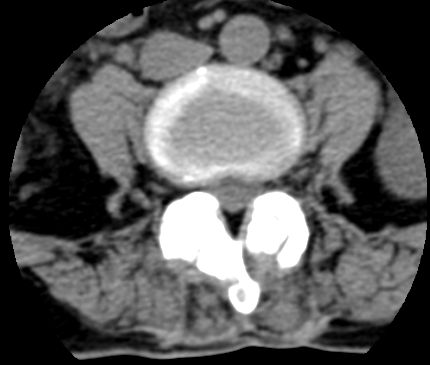

以下是引用余辉在2007-9-4 21:00:00的发言:[br]椎体棘突有点异常(像是被切割了),不知有否手术史,如椎体融合术等。单纯的退行性变可以出现椎间隙变窄,但同时一般会出现椎体上下缘的硬化增生,且椎体间完全融合的机率更小,本例椎体完全融合且椎体上下皮质缘破坏掉了,如果没有手术史,就应该考虑椎间盘炎性病变了,且椎体棘突及棘间韧带的变化也并不是不支持这个,多数小关节也融合了,且其形态也容易让人联想到如强脊炎及类风关等病变。[br][br][本贴已被 余辉 于 2007-9-4 21:03:55 修改过]

以下是引用chry3在2007-9-4 20:42:00的发言:[br]椎间盘病史?是什么样的病史,无双下肢放射痛,那就不是椎间盘突出了。是感染、什么性质的?[br]从图象看椎间隙消失,椎间盘组织未见,锥体滑脱是因为椎间盘溶解造成的[br]l4、5椎体骨质结构未见异常,l5上缘是l4的长期压迫所致[br]还是考虑椎间盘感染,结核。[br]